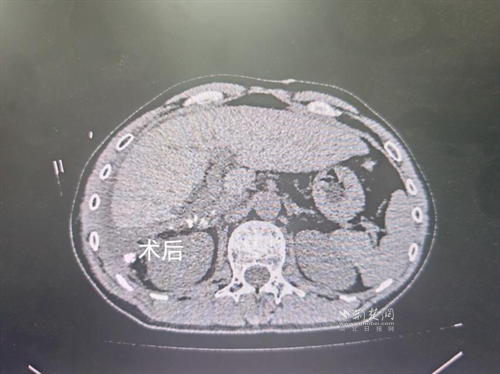

經(jīng)過(guò)肝膽外科牽頭組織的多學(xué)科MDT會(huì)診,團(tuán)隊(duì)確認(rèn)其適合接受當(dāng)前國(guó)際先進(jìn)的釔90樹脂微球選擇性內(nèi)放射治療。治療僅一個(gè)月后,患者病灶即從10cm縮小至6cm;術(shù)后六個(gè)月復(fù)查顯示,病灶體積進(jìn)一步縮小近40%,影像學(xué)檢查提示完全緩解,臨床分期成功轉(zhuǎn)化,達(dá)到手術(shù)切除標(biāo)準(zhǔn)。